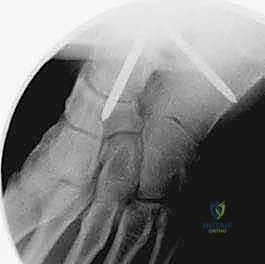

- التصوير المقطعي المحوسب (CT Scan): إجراء بالغ الأهمية قبل الجراحة. يوفر صوراً ثلاثية الأبعاد للعظام، مما يساعد الدكتور هطيف في تقييم جودة العظم بدقة، تحديد حجم التكيسات العظمية، والتخطيط الهندسي الدقيق لزوايا إدخال البراغي الجراحية.

هو إحداث توازن مثالي بين الجراحة المفتوحة وجراحة المناظير. يقوم الأستاذ الدكتور محمد هطيف بإجراء الجراحة عبر شقين أو ثلاثة شقوق صغيرة جداً (لا تتجاوز 2-4 سم). من خلال هذه النوافذ الصغيرة، وباستخدام أدوات جراحية دقيقة ومخصصة، يتمكن من الرؤية المباشرة للمفصل، وإزالة الغضاريف التالفة بالكامل، وتجهيز العظام للدمج، ثم تثبيتها بالبراغي.